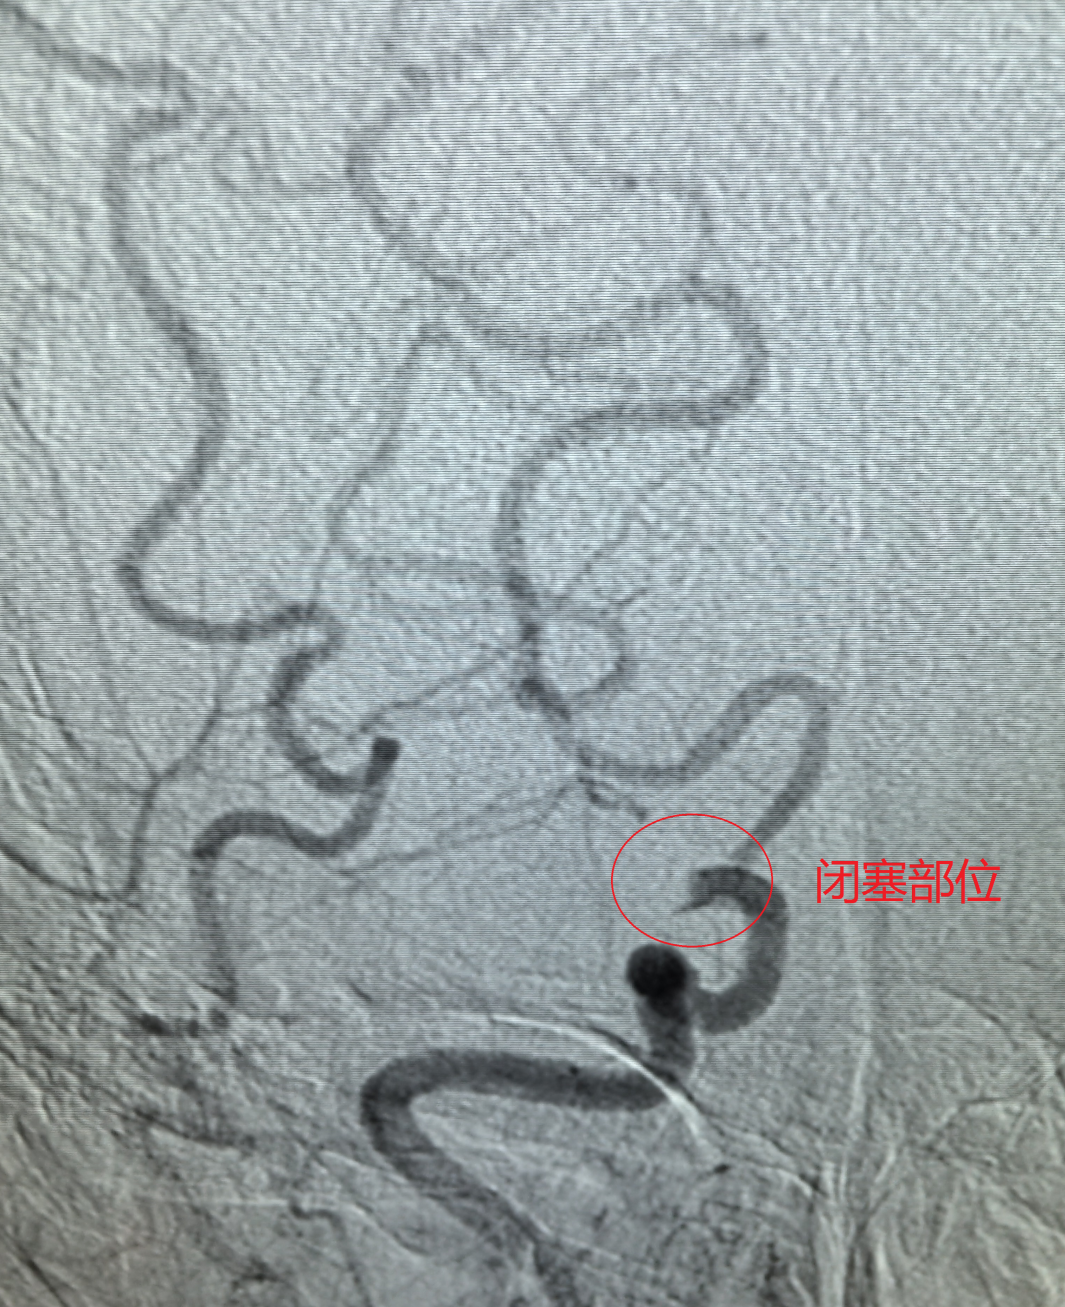

“精湛医术保健康,高尚医德为患者”!近日,一面承载着患者全家深深感激的锦旗,被赠送到葫芦岛市第二人民医院神经介入科钟强主任及陆阔医师手中。锦旗背后,是一场与死神赛跑的生命奇迹,钟强主任团队凭借高超的神经介入技术与多学科无缝协作,成功为一名急性大面积脑梗死危重患者施行高难度取栓手术,打通了被顽固血栓“死死封堵”的极细血管,最终助力患者获得良好康复。

挑战极限:“绣花功夫”疏通“生命狭道”